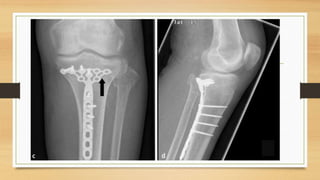

TTO POSOPERATORIO:

– Elevar la extremidad en una férula por 5 días o dispositivo de movilización pasiva

– Ortesis se retira cuando el paciente tiene control cuadricipital (7 – 10 día se consigue

una flexión de 90°).

– Fracturas tipo B o C permacen con carga parcial (10 – 15 Kg.) o sin carga, aproximadamente

de 6 – 8 semanas.

– Se permite mayor carga, hasta el 50% del peso corporal, después de las 6 – 8 semanas.

– Pacientes con fracturas de alta energía (lesiones B3 y C3) la carga total debe aplazarse 12 a 16

semanas.